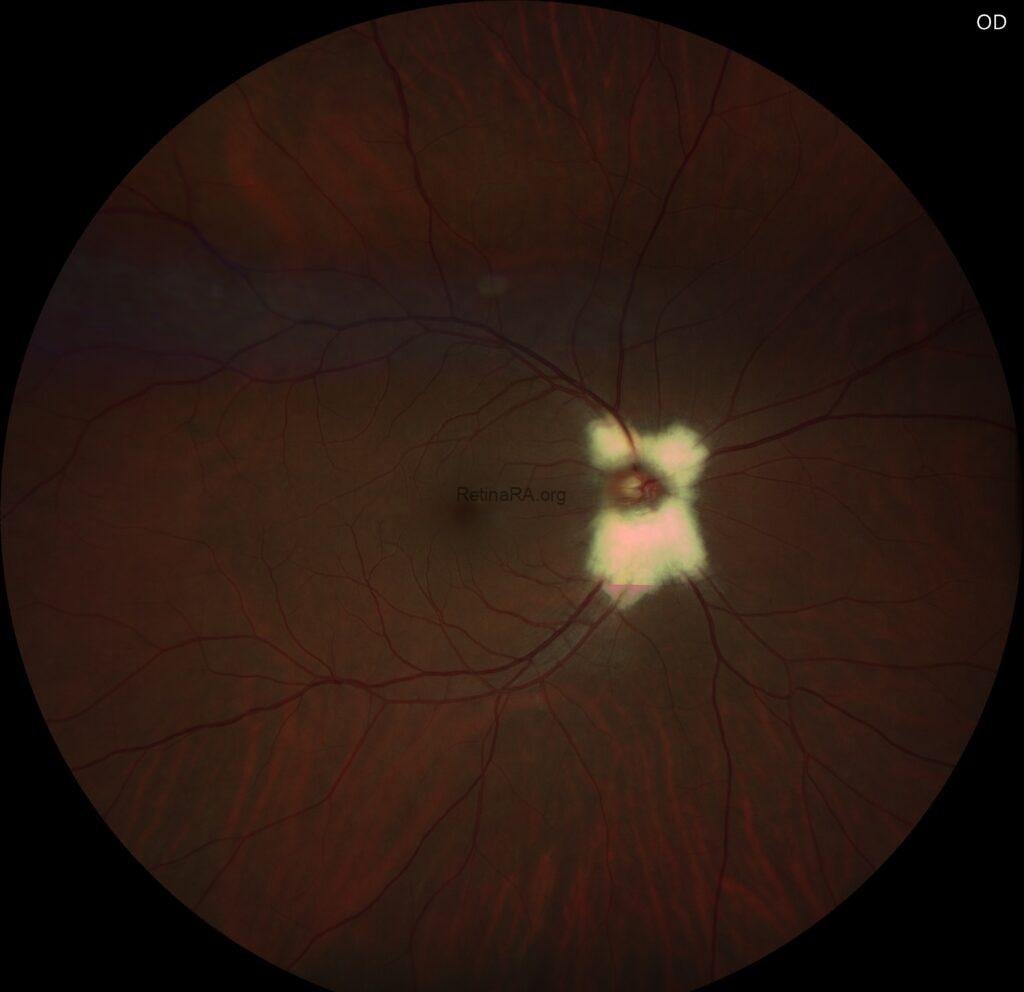

Fundus examination revealed a peripapillary, white-gray, striated patch with feathered borders, approximately one disc diameter in the right eye and half a disc diameter in the left eye.

Optical coherence tomography scans through these lesions demonstrated a thickened and hyperreflective retinal nerve fiber layer.

Fundus autofluorescence showed corresponding hypoautofluorescence at the lesion sites.

Myelinated retinal nerve fibers are a rare, benign finding in the eye. Normally, retinal nerve fibers are unmyelinated, but in MRNF, myelin extends into the retina, appearing as white or gray striated patches near the optic disc. They are usually discovered incidentally during routine eye exams and are typically asymptomatic. While vision is often normal, MRNF can sometimes be associated with high myopia or amblyopia. Optical coherence tomography (OCT) shows a thickened, hyperreflective retinal nerve fiber layer corresponding to the lesion. No treatment is needed, but regular monitoring is recommended to rule out other retinal pathologies.